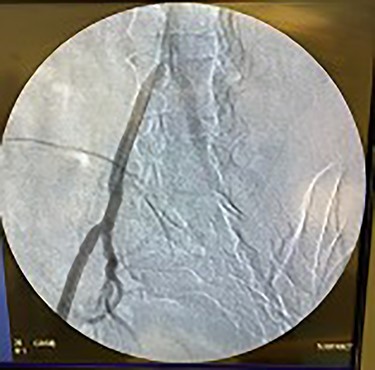

Catheter arteriogram results showed significant occlusion of the left iliac artery (Figs 3 and 4), the right iliac artery (Fig. 1), as well as the distal abdominal aorta (Fig. 2). There were numerous collateral vessels noted, indicating the presence of long-standing proximal stenosis (Fig. 1). The decision was made to use angioplasty to help widen the areas of stenosis. An 8 mm × 40 mm Passeo balloon was advanced from the right femoral artery into the left iliac artery (Fig. 7) and insufflated to 6 mmHg (Fig. 6). The balloon was allowed to remain expanded for 1 min and then was deflated. Next, the distal aorta was repaired in a similar fashion. The balloon was advanced into the distal aorta from the right femoral access and insufflated to 12 mmHg (Fig. 8). The balloon was allowed to remain expanded for 90 s.

Fluoroscopy of bilateral iliac arteries showing significant arterial disease.